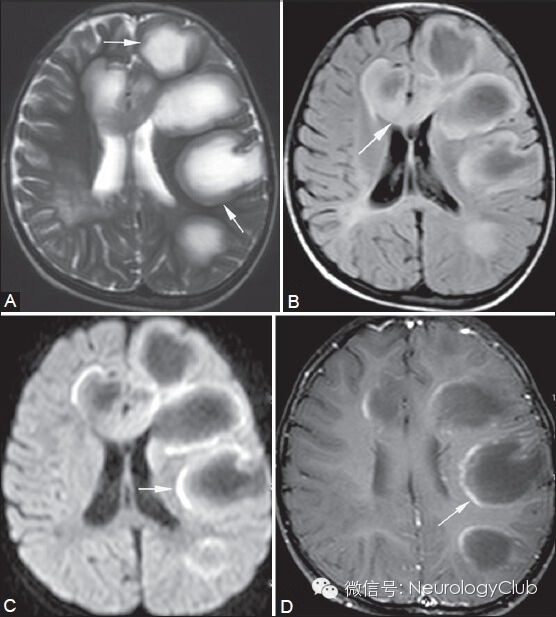

[概述]开环征(open-ring sign),又称为“弓形征”(arclike sign),是一种特殊的强化方式,指静脉注射对比剂后,病灶中心不强化,而其外围组织呈现出非闭合性的环形强化。Masdeu等于1996年首先描述这种特殊的影像学征象,并认为其对不典型脱髓鞘病的诊断有高度特异性。

[常见疾病]多发性硬化

(男,36岁,左侧面部及肢体麻木7月余,加重4天。引自:多发性硬化的常见MRI征象分析. 磁共振成像 2011年第2卷第4期)